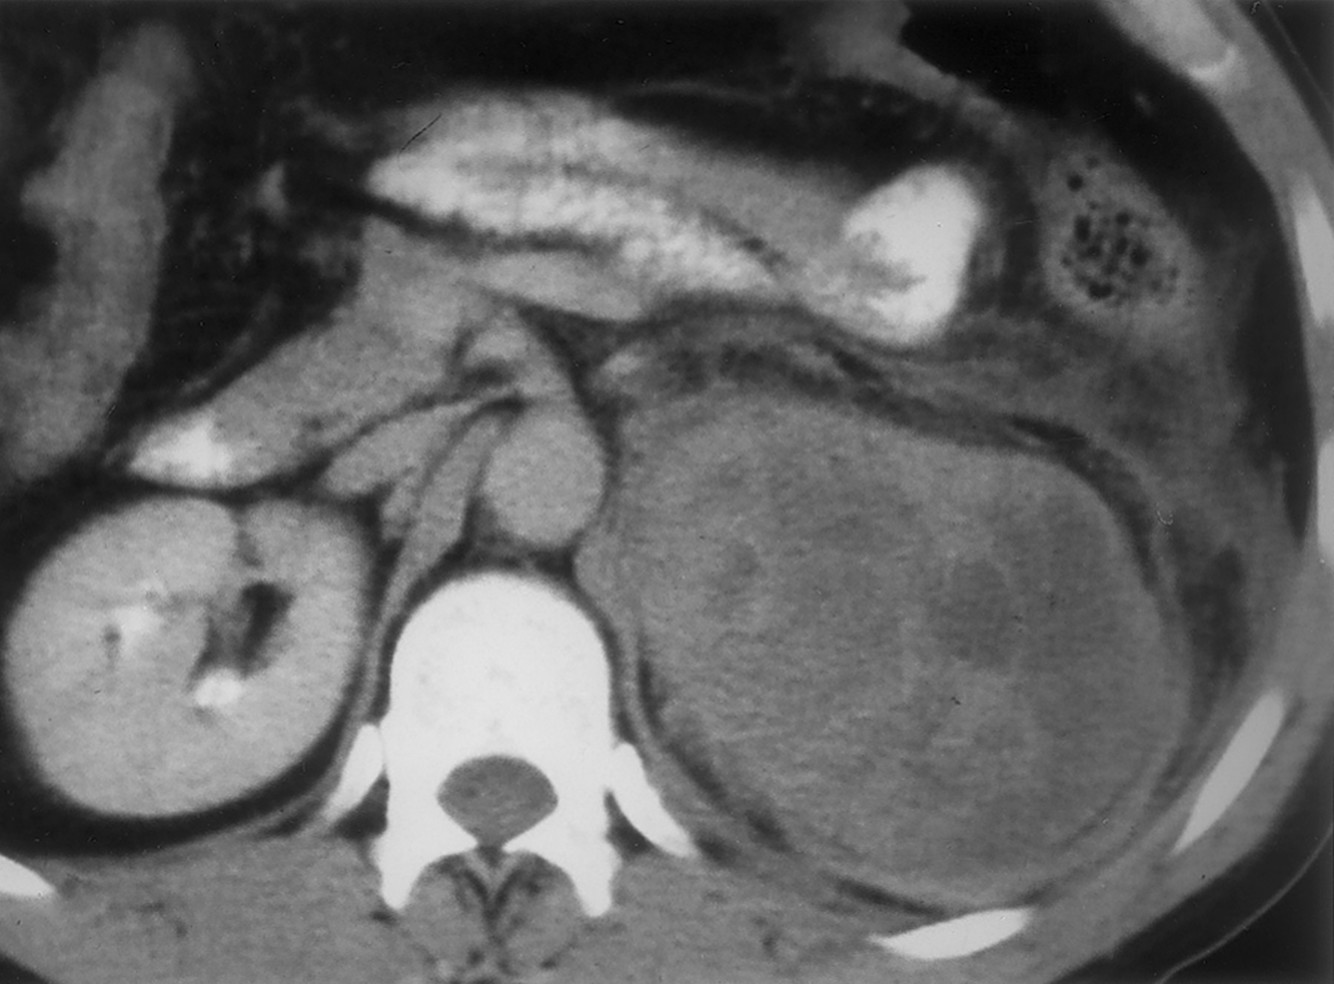

Adrenal CORTICAL carcinoma

as opposed to the medullary - pheochromocytoma